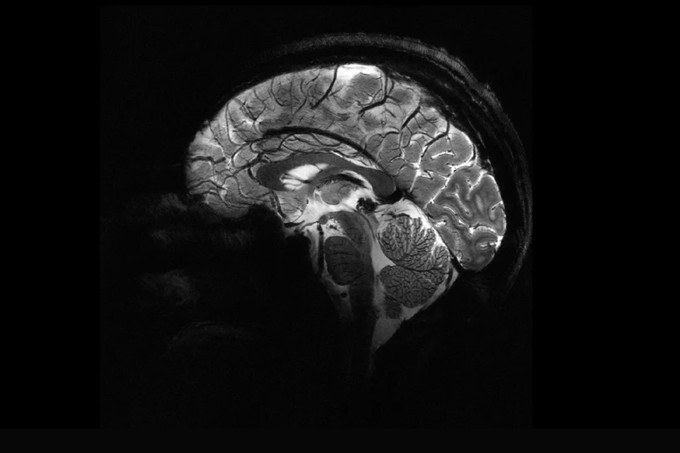

Ez a szervünk saját magát tanítja, gyógyítja vagy programozza újra!

Az agy hihetetlenül rugalmas - folyamatosan változik és lenyűgöző, öngyógyító, önfejlesztő képességekkel rendelkezik.